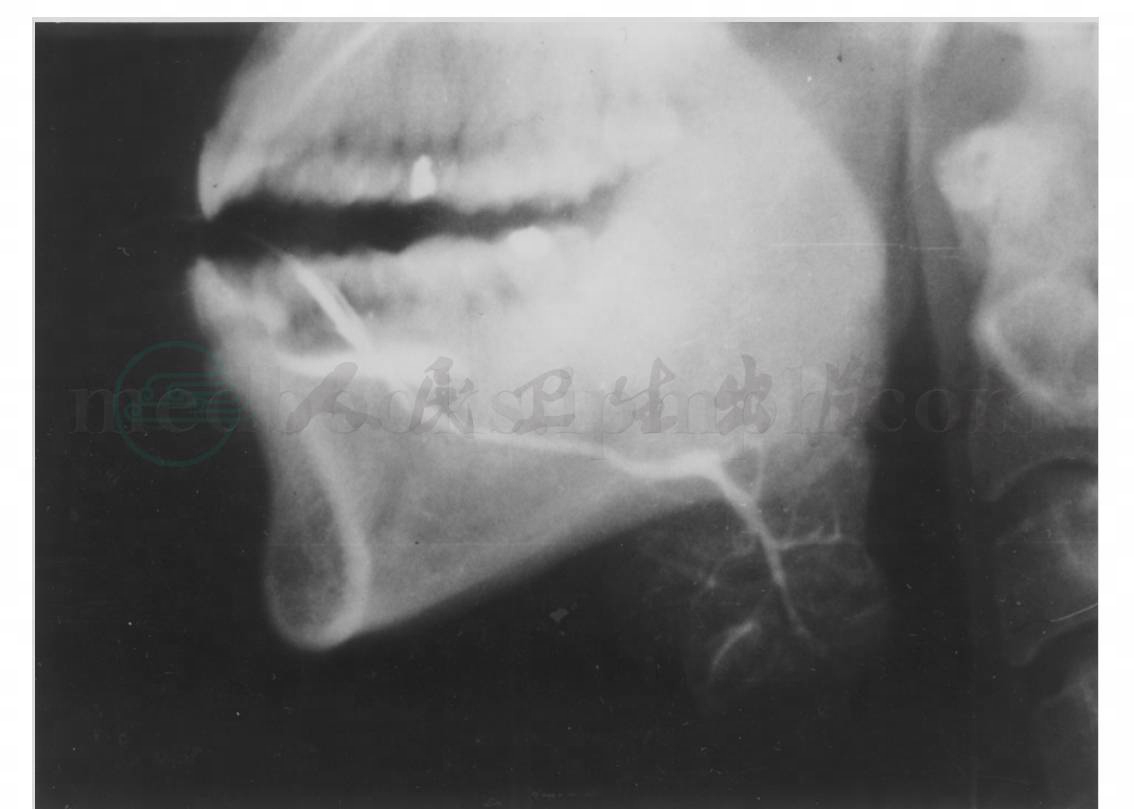

1. 腮腺造影侧位片

导管口位于上颌第二磨牙区,主导管在下颌升支上面斜向后下走行。正常导管长约5cm,最大管径0.9~4mm不等,平均2mm。在主导管上缘常分出副叶小分支,约半数人有一个或多个副腺体。由主导管分出的分支导管向上、向下走行,导管系统在腺体内一再分支,逐渐由粗至细,最后进入腺体组织,犹如叶脉。腺泡轻度充盈,显示为云雾状影像(图1)。

图1 正常腮腺造影侧位